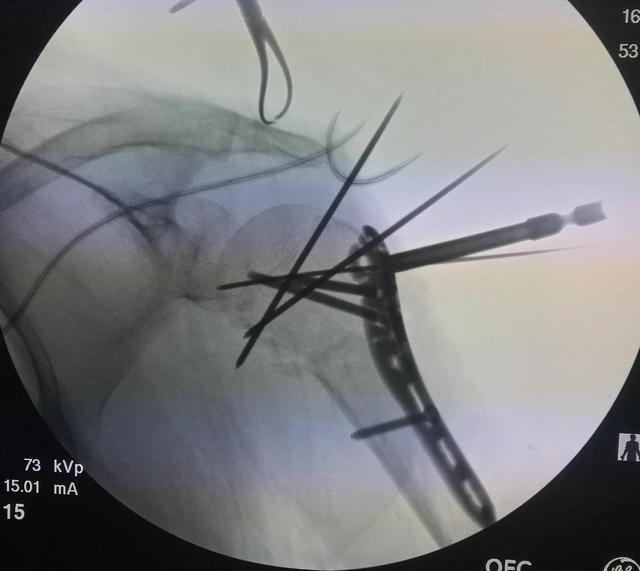

手术治疗的方法主要有闭合穿针内固定、闭合带锁髓内针加空心钉内固定、切开复位钢板内固定、改良克氏针张力带内固定等。主要手术方式包括:

髓内钉固定治疗

髓内钉固定治疗肱骨外科颈骨折造成的创伤较小,能够保留骨折断端血供,可获得较高优良率。严重移位骨折,选择带锁髓内钉的方法治疗,尤其合并出现肱骨干骨折选择此种方法治疗有显著效果。对于改良带锁髓内钉,于近端主要利用螺旋刃锁钉有效完成角稳定,同普通带锁髓内钉进行比较,可增加骨内固定物解除效果,减少骨小梁劳损。用髓内钉固定方法治疗肱骨近端骨折,主要包括两种,分别为单针固定的方法以及多针固定的方法。

闭合复位经皮穿针固定术治疗

此种方法治疗可以防止过多对软组织造成剥离,促进骨折的愈合,降低肱骨头缺血坏死概率,配合早期肩关节功能锻炼可以获得显著效果。选择中空加压螺纹钉治疗可以获得理想效果,不但可以将骨折断面进行有效固定,加强骨折稳定性,并且骨折断面有一定的压应力,对骨折断面紧密接触有促进作用,可缩短骨折愈合时间,降低并发症概率。